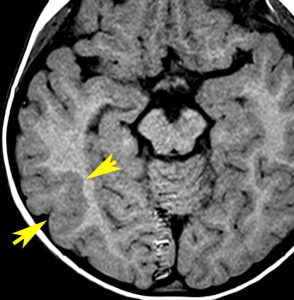

2歳時に偶然発見された,大脳皮質の限局性異形成です。10歳まで症状はでていません。

右側頭葉中側頭回の皮質が厚くなっています。T1強調画像では等信号で見づらいですが,下のフレア画像とT2強調画像では高信号になるのでわかります。

低悪性度グリオーマと間違われることがありますが,大脳皮質だけが異常な信号になっていて,皮質下白質に異常所見がないことが鑑別点です。